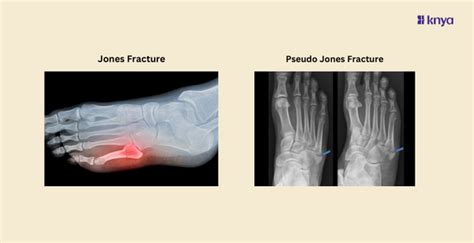

Learn the Difference Between Jones and Pseudo Jones Fracture – Knya

knyamed.com